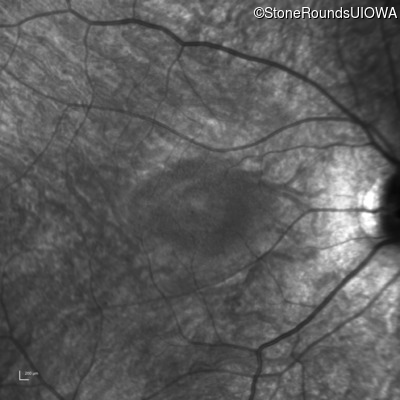

Infrared Fundus Photograph - Right - 20/60

Exemplar